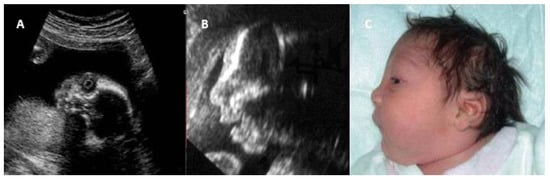

- Migliucci, A.; Di Fraja, D.; Sarno, L.; Acampora, E.; Mazzarelli, L.L.; Quaglia, F.; Mallia Milanes, G.; Buffolano, W.; Napolitano, R.; Simioli, S.; et al. Prenatal diagnosis of congenital rubella infection and ultrasonography: A preliminary study. Minerva Ginecol. 2011, 63, 485–489. [Google Scholar]

| Intrauterine Findings | Description | Imaging Methods |

|---|---|---|

| Intrauterine growth restriction | Fetal size below expectations for gestational age | US |

| Microcephaly | Fetal head circumference below normal | US, MRI |

| Ventriculomegaly/calcifications | Cerebral ventricle dilation or intracranial calcifications | US, MRI |

| Hydrops fetalis | Fluid accumulation in fetal compartments and subcutaneous tissue | US |

| Congenital heart disease | ASD, VSD, PDA | Doppler US, fetal cardiac MRI |

| Hepatosplenomegaly | Enlarged liver and spleen | US |

| Pleural effusion/ascites | Fluid accumulation in pleural or abdominal cavities | US |

| Cataract and microphthalmia | Lens opacity and small eye dimensions | Ocular US, MRI |

| Liver hypoechogenicity | Low echogenic areas suggesting inflammation or infection | US |

| Pulmonary artery stenosis | Narrowing of the pulmonary artery | Doppler US, fetal cardiac MRI |

| Echogenic bowel | Increased bowel echogenicity, similar to bone | US |

| Polyhydramnios | Excess amniotic fluid | US |

| Placentomegaly | Thickened placenta for gestational age | US |